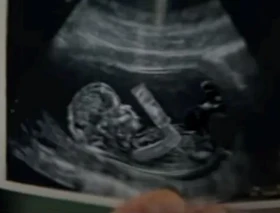

Anuncio de Pringles fue el más provida del Super Bowl

El domingo 12 de febrero Pringles emitió durante el Super Bowl un simpático anuncio que, posiblemente de forma accidental, contenía un sorprendente mensaje...